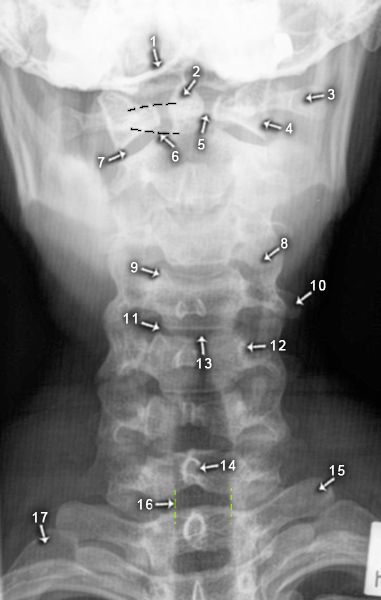

Wirbelsäule

HWS a.p.

1. Okzipurt

2. Dens axis

3. Processus transversus C1

4. Massa lateralis (von C1)

5. Articulatio atlantoaxialis mediana

6. Arkus

7. Articulatio atlantoaxialis lateralis

8. überlappende Gelenkfortsätze

9. Processus uncinatus

10. Processus transversus C4

11. Unkovertebralgelenk

12. Pediculus arcus vertebrae

13. Zwischenwirbelraum

14. Processus spinosus

15. Processus transversus vertebrae thoracicae I

16. Tracheaaufhellungsband

17. Costae I (1. Rippe)